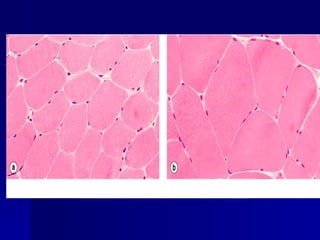

Atrofia muscular

(Tricrómico) 1

adelgazamiento de las

fibras musculares y

reemplazo por

colágeno maduro (azul.

ATROFIA ATROFIA Atrofia muscular Atrofia muscular (Tricrómico)1 (Tricrómico) 1 adelgazamiento de las adelgazamiento de las fibras musculares y fibras musculares y reemplazo por reemplazo por colágeno maduro (azul. colágeno maduro (azul.